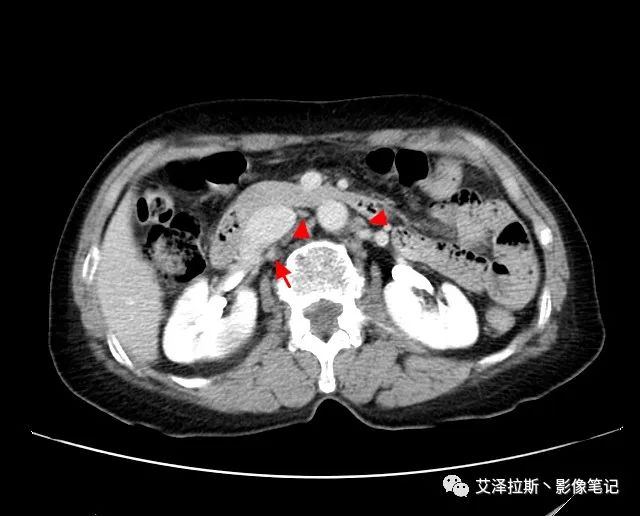

以下為累及的區(qū)域淋巴結(jié),共計15個區(qū)域:

【影像所見】 胃竇部狹窄,胃壁環(huán)形增厚,小彎側(cè)見一巨大潰瘍,周圍伴“環(huán)堤征”,漿膜面不完整,胃周脂肪見網(wǎng)格狀條索影,病灶與肝臟左葉、胰腺鉤突脂肪間隙消失,增強(qiáng)掃描病灶明顯強(qiáng)化。引流區(qū)內(nèi)約15個區(qū)域淋巴結(jié)受累。

【診斷意見】 胃竇部胃癌(T4N3期) 該病例腫塊突破漿膜層,與肝臟左葉、胰腺鉤突分界不清,脂肪界面消失,定為T4期; 受累及的淋巴結(jié)為15個區(qū)域,定為N3; 有無遠(yuǎn)處轉(zhuǎn)移尚不明確,所以M期暫時無法確定。